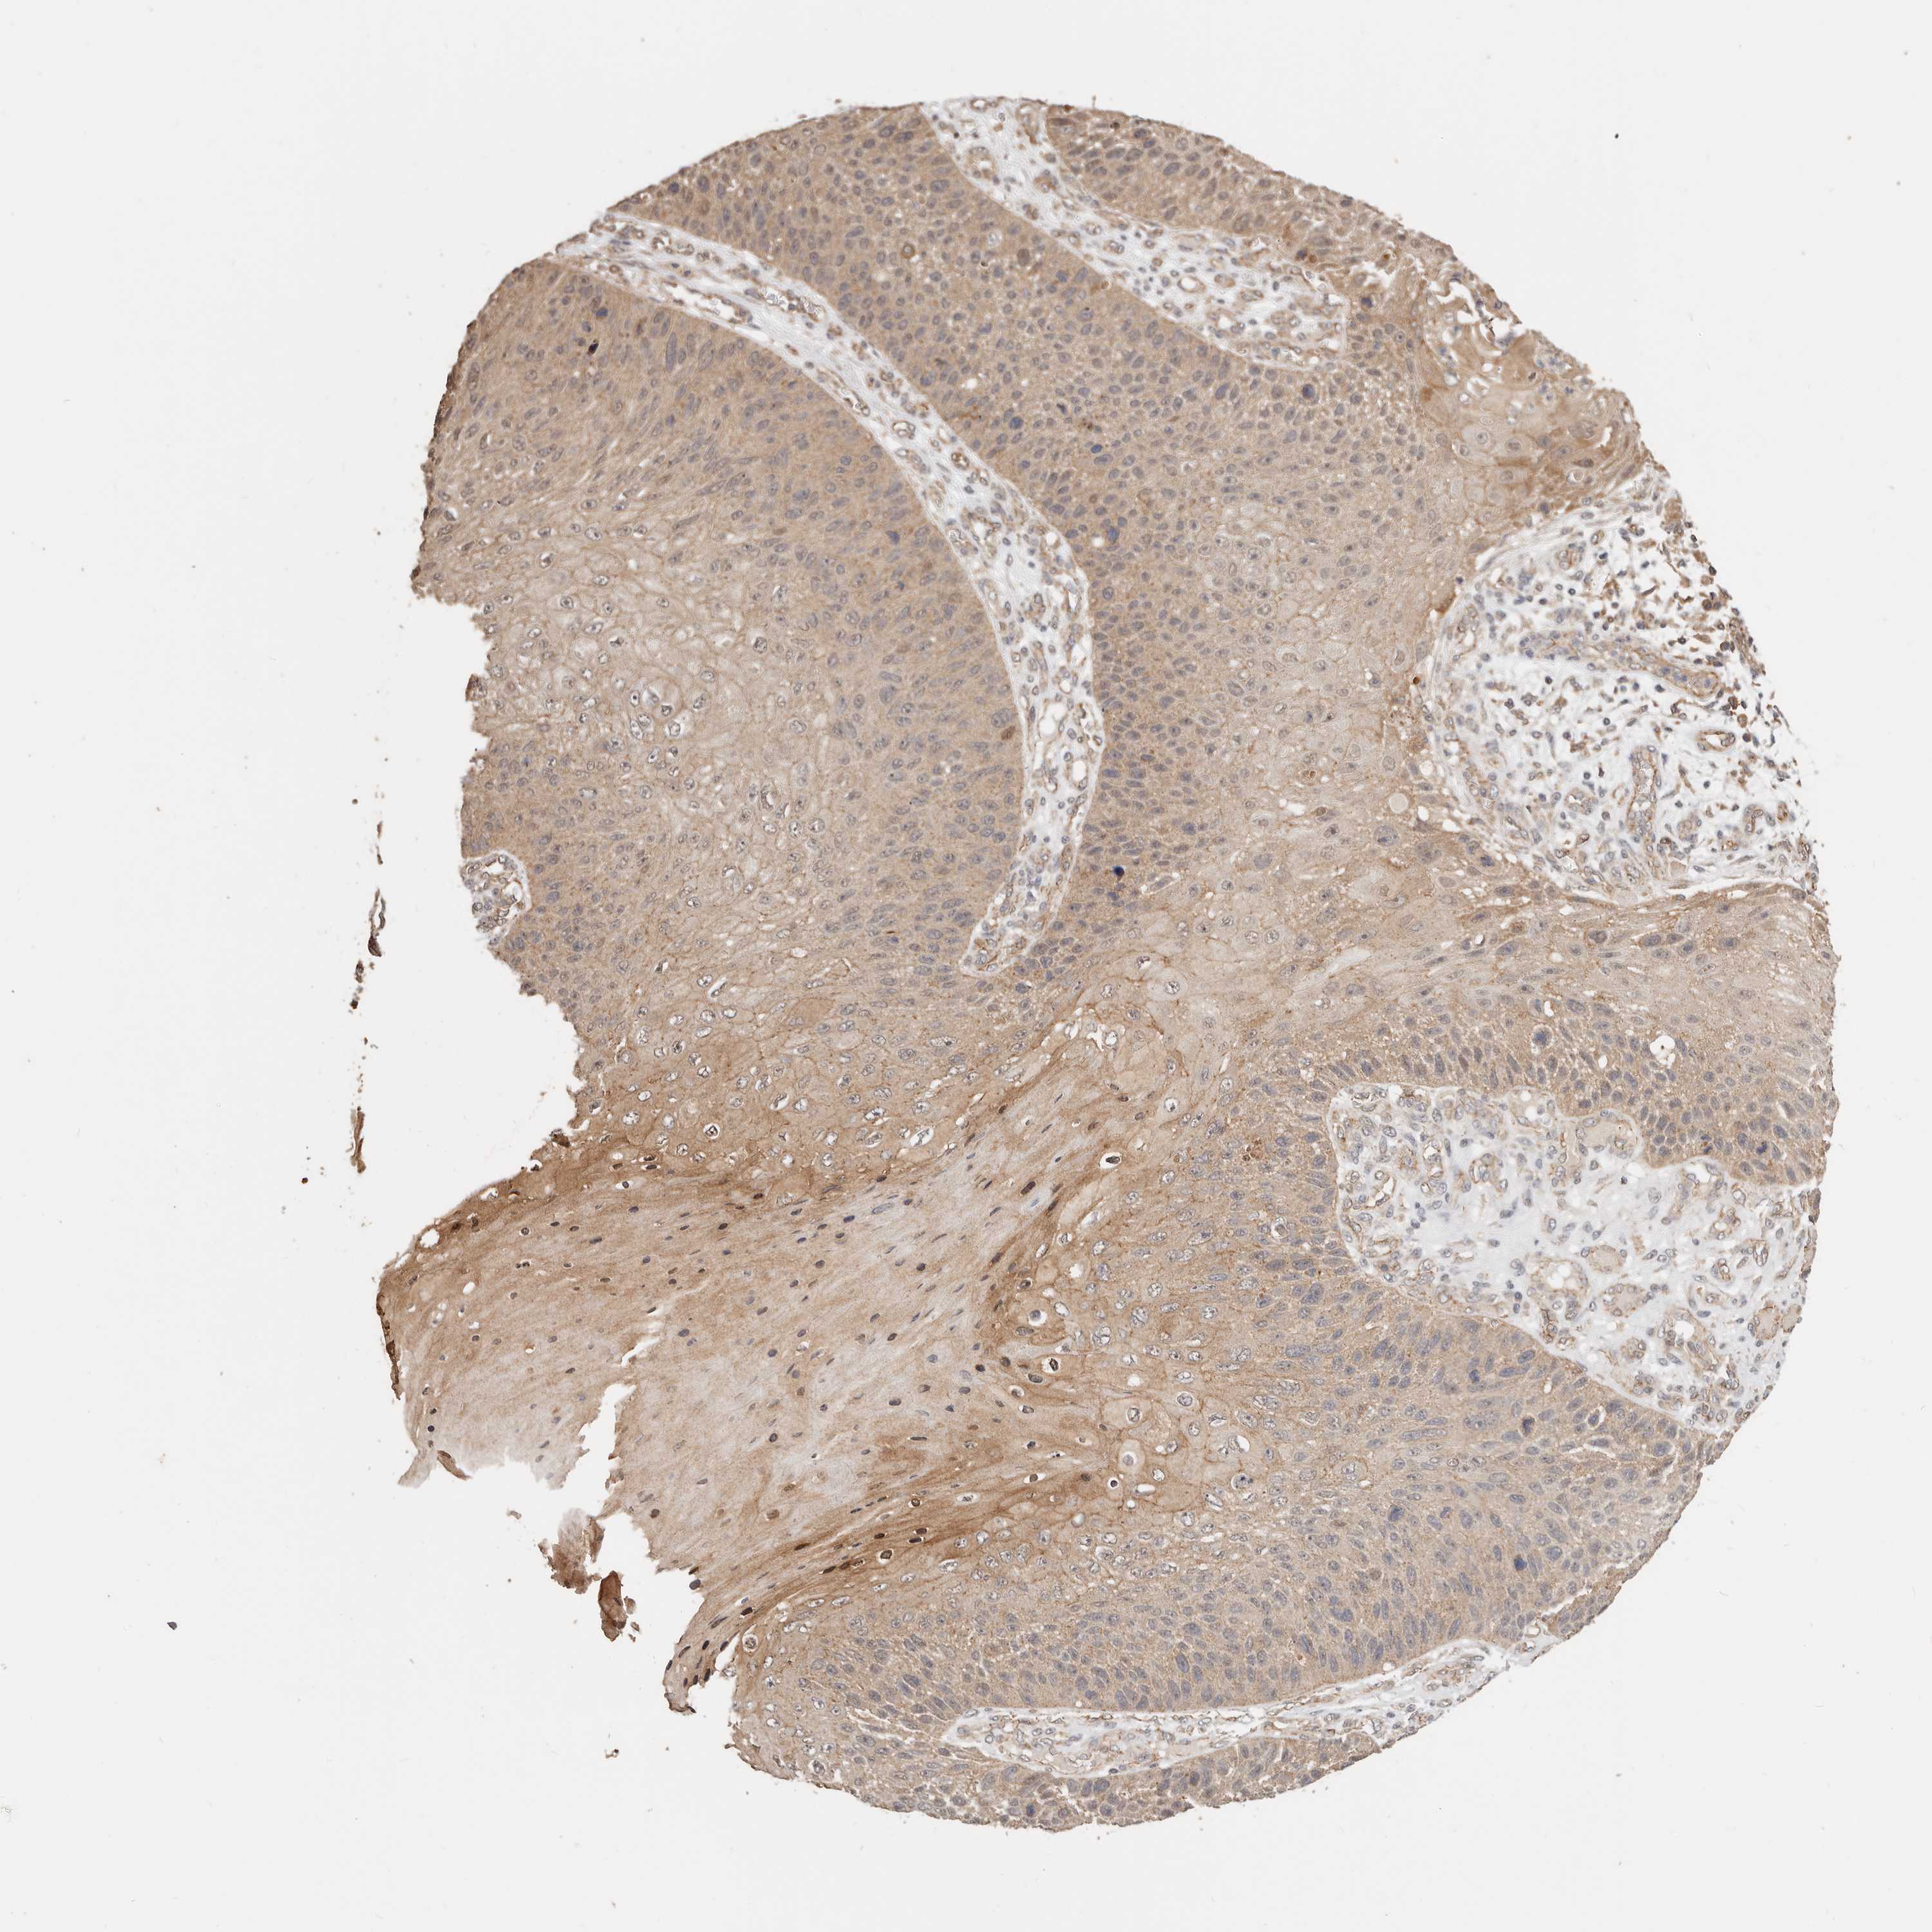

SKIN CANCER - Protein expressioni

A mouse-over function shows sample information and annotation data. Click on an image to view it in a full screen mode. Samples can be filtered based on level of antibody staining by selecting one or several of the following categories: high, medium, low and not detected. The assay and annotation is described here.

Antibody stainingi

Antibody staining in the annotated cell types in the current human tissue is reported as not detected, low, medium, or high, based on conventional immunohistochemistry profiling in selected tissues. This score is based on the combination of the staining intensity and fraction of stained cells.

Each image is clickable and will lead to virtual microscopy that enables deeper exploration of all samples and also displays staining intensity scores, fraction scores and subcellular localization as well as patient and tissue information for each sample.

HPA030212

HPA030213

HPA030214

HPA030215

CAB013496

Basal cell carcinoma

Squamous cell carcinoma, NOS

Squamous cell carcinoma, metastatic, NOS

Adnexal tumor, benign